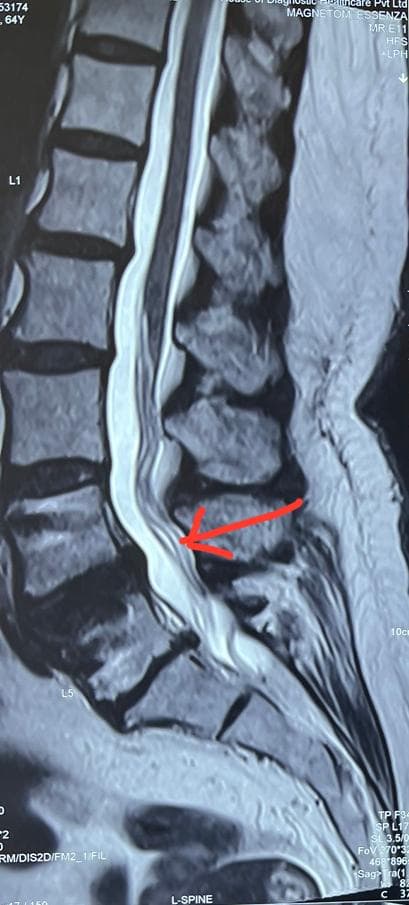

- Spinal canal stenosis is condition of spine where spinal canal become narrow. This put pressure over the spinal cord and nerves passing through it.

The diagnosis depends on complaints and a physical examination. Following are some examples: